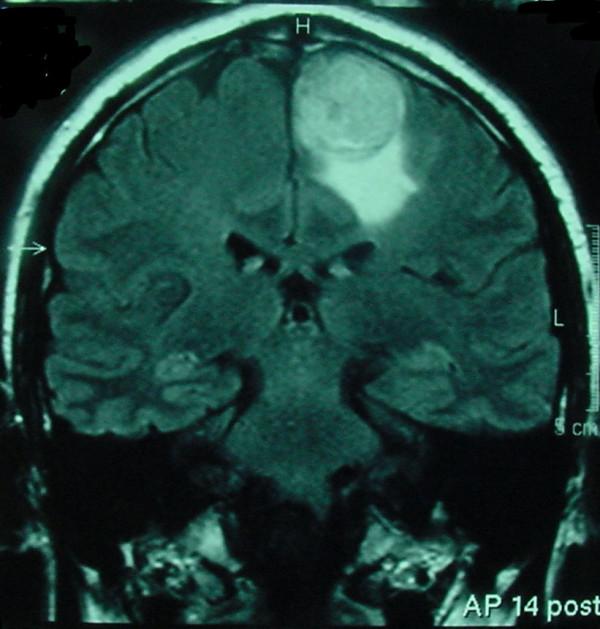

A 47-year-old man presented in July 1999 with a jejunal GIST with multiple hepatic metastases. The jejunal primary was resected and after unsuccessful cytoreductive chemotherapy, the liver metastases were also resected in December 1999. The patient subsequently relapsed in August 2001 with symptomatic hepatic, subcutaneous gluteal, left choroidal and right ocular metastases all confirmed on CT and PET scanning. Biopsy confirmed recurrent GIST. MRI and lumbar puncture excluded central nervous system involvement. The patient was commenced on imatinib 400 mg bd in September 2001 through a clinical trial. The symptoms improved with objective PET and CT scan response until December 2002 when the patient developed a right-sided foot drop. MRI scan showed a left parasagittal tumor which was resected and confirmed histologically to be metastatic GIST. Imatinib was ceased pre-operatively due to the trial protocol but recommenced in February 2003 on a compassionate use program. The left parasagittal metastasis recurred and required subsequent re-excision in September 2003 and January 2004. Control of the systemic GIST was temporarily lost on reduction of the dose of imatinib (due to limited drug supply) but on increasing the dose back to 800 mg per day, systemic disease was stabilized for a period of time before generalised progression occurred.

一名47岁男性于1999年7月就诊,患有空肠GIST并伴有多处肝转移。空肠原发灶被切除,在减瘤化疗失败后,肝转移灶也于1999年12月被切除。患者随后于2001年8月复发,出现有症状的肝、皮下臀肌、左侧脉络膜和右侧眼部转移,CT和PET扫描均证实。活检确诊为复发性GIST。MRI和腰椎穿刺排除了中枢神经系统受累。通过一项临床试验,患者于2001年9月开始服用伊马替尼,每日400mg,分两次服用。症状改善,PET和CT扫描显示有客观反应,直到2002年12月患者出现右侧足下垂。MRI扫描显示左侧矢状旁肿瘤,切除后经组织学证实为转移性GIST。由于试验方案,伊马替尼在术前停用,但于2003年2月根据同情用药计划重新开始使用。左侧矢状旁转移灶复发,随后分别于2003年9月和2004年1月再次切除。由于伊马替尼剂量减少(由于药物供应有限),全身GIST的控制暂时丧失,但将剂量增加回每日800mg后,全身疾病在广泛进展之前稳定了一段时间。